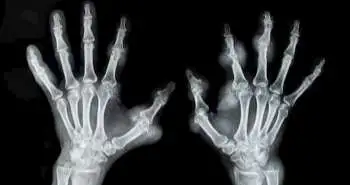

Correlation between smoking and fish intake with risk of rheumatoid arthritis

Attempts are proceeding to identify risk factors for rheumatoid arthritis (RA). Where smoking is an essential risk factor for RA, many individuals who never smoked also develop RA, this indicates the involvement of other factors such as diet and obesity as well. Other previous studies say that eating fish is a protective approach for rheumatoid arthritis (RA) risk possibly due to the anti-inflammatory influence of omega-3 fatty acid it contains, although this association has not been established explicitly. Therefore, this prospective cohort study was conducted with large sample size, repeated measures of dietary intake, and extended follow-up to assess the fish intake and RA risk by the age of onset, smoking and serologic status.